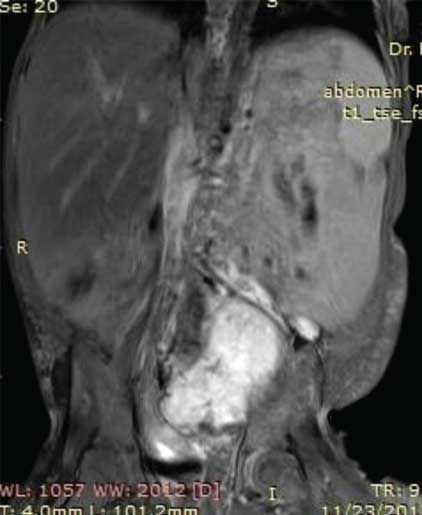

On MRI abdomen, mass was visualised in the lower abdomen, dipping into the false pelvis to the left of midline, was solid with few foci of calcification, isointense to hyperintense to muscle on T1 images and hyperintense to muscle on T2 images [Table/Fig-3a,b]. On sagittal and coronal MR the mass was seen to be pre-vertebral and retroperitoneal, with intense homogenous enhancement indicating its vascularity, and was clearly separate from the uterus and ovaries [Table/Fig-4a]. Based on the imaging characteristics, we opined the mass to be immature germ cell retroperitoneal tumour.

Axial T1 weighted VIBE MR Image demonstrates a T1 hyperintense solid mass occupying the lower abdomen and left side of pelvis. The mass is separate from the uterus and ovaries.

Axial T2 weighted MR image show the mass to be retroperitoneal in location with heterogeneously hyperintense signal intensity. The mass is seen abutting the left internal iliac artery and vein which are enlarged in comparison to the right iliac vessels. There is significant associated hypertrophy of the subcutaneous and muscular tissues of the leftthoraco-abdominal walldorsally and ventrally.

Post gadolinium Coronal T2 MR Image demonstrates intense enhancement of the mass with displacement of the adjacent bowel loops.